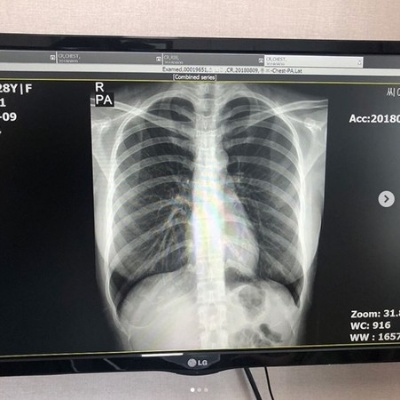

近期,丰岛心樱在社交平台上公开了自己的肺部X光片,引发了热议。此举不仅展现了她的健康状况,也因日本写真偶像极少公开此类个人医疗信息而备受关注。

写真偶像直接公开X光片的情况非常少见,一方面涉及医疗法规,专业人士也能通过此类影像观察胸部构造,从而间接印证其是否为纯天然、未经整形。

粉丝们的反应充满趣味,有人赞叹“连X光片都如此性感”“这馅饼真漂亮。它是无菸馅饼。”,有人则专业点评其肺部“这张胸部正位X光片显示肺部状况极佳。双肺野清晰,未见浸润、结节或胸腔积水。心脏轮廓正常,胸廓骨骼未见骨折或异常。”,有人认为这展现了独特的内在美“你的X光片看起来如此美丽,证明你很健康。希望你继续保持这份光彩。”